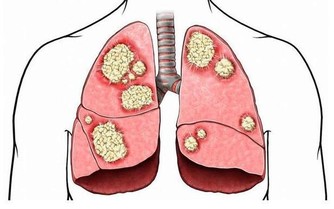

2、外界環境中的細菌易隨吸氣進入呼吸道及肺部。

(健康隱患:呼吸係統疾病)